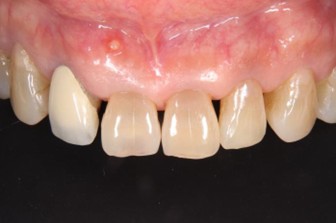

20代 男性

治療前

治療後

治療後- リスク・副作用

(薬・注射・レントゲン・CT・データ分析・骨造成・サージカルステント・血液検査・仮歯) - 年齢/性別

- 20代/男性

- 患者の具体的な症状

- 1年前に左上12 右上1の根の治療をし、その後放置していたら、左上2が破折した。

左上2インプラント補綴 左上1右上1オールセラミック装着。

歯根破折と虫歯による痛み、審美障害を主訴として来院。 - 検査方法

- コーンビームCT、レントゲン撮影

- 診断結果

- 左上2 歯根破折

- 治療詳細

- 左上抜歯後、インプラント埋入1本

骨造成あり 局所麻酔

インプラント治療後、左上1右上1セラミック修復2本 - 通院回数

- 9回

- 治療期間

- 12か月